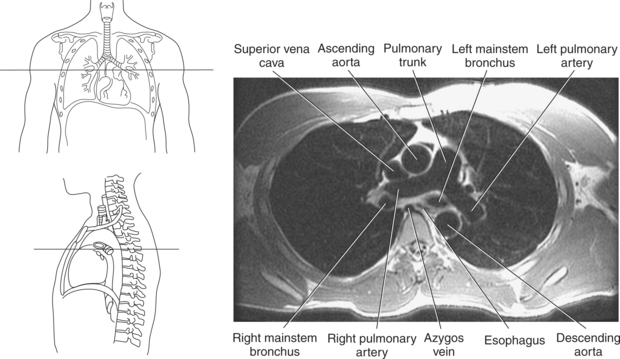

Blood travels to and from the heart through the great vessels, which include the aorta, pulmonary arteries and veins, and superior and inferior venae cavae (Figures 6.54 and 6.55). The aorta is the largest artery of the body and can be divided into the ascending aorta, aortic arch, and descending aorta. The ascending aorta begins at the base of the left ventricle at the level of the sternal angle, then curves superiorly and posteriorly as the aortic arch over the root of the left lung. The top of the aortic arch is approximately at T3 (Figures 6.56 and 6.57). The arch continues as the descending aorta posterior to the left bronchus and pulmonary trunk, on the left side of the vertebral body of T4 (Figures 6.58 and 6.59). The descending aorta passes slightly anterior and to the left of the vertebral column as it descends through the thoracic and abdominal cavities (Figure 6.60). While in the thoracic cavity, the descending aorta is commonly called the thoracic aorta, and while in the abdominal cavity, it is called the abdominal aorta. The pulmonary trunk is the origin of the right and left pulmonary arteries and lies entirely within the pericardial sac. It arises from the right ventricle and ascends in front of the ascending aorta, courses posteriorly and to the left, where it bifurcates at the level of the sternal angle (T4) into the right and left pulmonary arteries (Figures 6.61 through 6.63). The pulmonary trunk is attached to the aortic arch by a fibrous cord called the ligamentum arteriosum, the remnant of an important fetal blood vessel (ductus arteriosus) that links the pulmonary and systemic circuits during fetal development (Figures 6.54 and 6.61). The right pulmonary artery courses laterally, posterior to the ascending aorta and superior vena cava, and anterior to the esophagus and right mainstem bronchus, to the hilum of the right lung. At the root of the right lung, the right pulmonary artery divides into two branches, with the lower branch supplying the middle and inferior lobes and the upper branch supplying the superior lobe (Figures 6.61 through 6.64). The left pulmonary artery, shorter and smaller than the right, is also the most superior of the pulmonary vessels. It travels horizontally, arching over the left mainstem bronchus, and enters the hilum of the left lung just superior to the left mainstem bronchus (Figures 6.61 through 6.64). Within the lungs, each pulmonary artery descends posterolateral to the main bronchus and divides into lobar and segmental arteries, continuing to branch out and to follow along with the smallest divisions of the bronchial tree (Figures 6.61 and 6.64). Located inferior to the pulmonary arteries are the four pulmonary veins, two each (superior and inferior) extending from each lung to enter the left atrium (Figures 6.54, 6.55, 6.61, and 6.64 through 6.68). They commence in a capillary network along the walls of the alveoli, where they are continuous with the capillaries of the pulmonary arteries. The venous capillaries merge to form small vessels that unite successively to eventually form a single trunk for each lobe: three for the right and two for the left lung. Frequently the trunk from the middle lobe of the right lung unites with the trunk from the upper lobe, forming just two trunks on the right side prior to entering the left atrium. The right superior pulmonary vein collects blood from the upper lobe segments of the right lung and passes anterior and inferior to the right pulmonary artery, behind the superior vena cava. The right inferior pulmonary vein receives blood from the right lower lobes of the lung and crosses behind the right atrium to the left atrium (Figures 6.61 and 6.69 through 6.71). The left superior pulmonary vein receives blood from the left upper lobe of the left lung and courses anterior and inferior to the left main bronchus as it enters the left atrium. The left inferior pulmonary vein drains the inferior lobe of the left lung and passes toward the left atrium anterior to the bronchi (Figures 6.61 and 6.72 through 6.74). The pulmonary veins course more horizontally than the pulmonary arteries and are ultimately oriented toward the left atrium. At the root of the lungs, the pulmonary veins are anterior to the pulmonary arteries, which are anterior to the bronchus. While within the lungs, the branches of the pulmonary arteries are anterior to the bronchi, which are anterior to the pulmonary veins. The superior and inferior venae cavae are the largest veins of the body. The superior vena cava is formed by the junction of the brachiocephalic veins, posterior to the right first costal cartilage, and carries blood from the thorax, upper limbs, head, and neck (Figure 6.24). As it travels inferiorly, it is located posterior and lateral to the ascending aorta before entering the upper portion of the right atrium (Figures 6.54 through 6.59). The inferior vena cava is formed by the junction of the common iliac veins in the pelvis and ascends the abdomen to the right of the abdominal aorta and anterior to the vertebral column. It passes through the caval hiatus of the diaphragm and almost immediately enters the inferior portion of the right atrium (Figures 6.75 and 6.76).

Figure 6.59 Axial CT scan of chest with ascending and descending aorta.

Key: SVC, Superior vena cava; asa, ascending aorta; da, descending aorta; ca, carina;

Figure 6.63 Axial CT scan of chest with pulmonary trunk.

Key: SVC, Superior vena cava; pul, pulmonary trunk; asa, ascending aorta; da, descending aorta; rPA, right pulmonary artery; Az, azygous vein; lPA, left pulmonary artery.